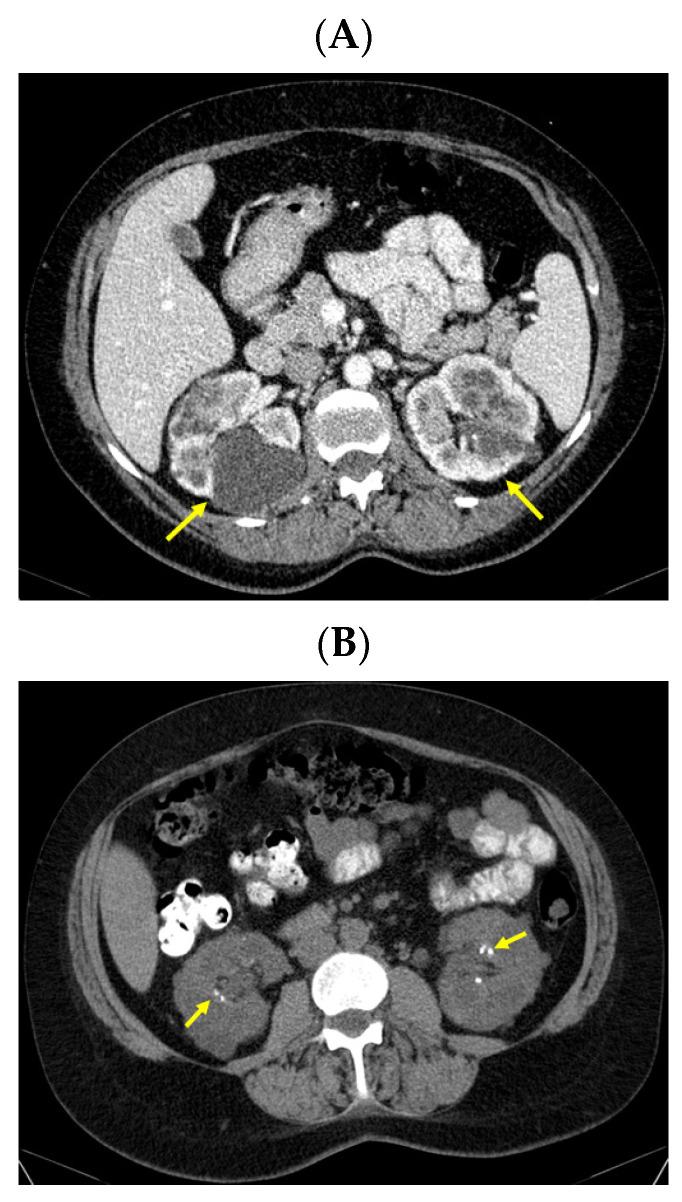

Brown tumors, an exceptional bone complication of severe primary (PHP) or renal (secondary) hyperparathyroidism (RHP), are caused by long-standing, elevated parathormone (PTH)-induced osteoclast activation causing multinucleated giant cell conglomerates with hemosiderin deposits in addition to the local production of cytokines and growth factors. We aim to present an adult case series including two females displaying this complication as part of a multidisciplinary complex panel in high PTH-related ailments. The approach was different since they had distinct medical backgrounds and posed a wide area of challenges amid real-life settings, namely, a 38-year-old lady with PHP and long-term uncontrolled hypercalcemia (with a history of pregnancy-associated PHP, the removal of a cystic jaw tumor, as well as a family and personal positive diagnosis of polycystic kidney disease, probably a PHP-jaw tumor syndrome), as well as, a 26-year-old woman with congenital single kidney and chronic renal disease-associated RHP who was poorly controlled under dialysis and developed severe anemia and episodes of metabolic acidosis (including one presentation that required emergency hemodialysis and was complicated with convulsive seizures, followed by resuscitated respiratory arrest). Both subjects displayed a severe picture of PHP/RHP with PTH levels of >1000 pg/mL and >2000 pg/mL and elevated serum bone turnover markers. Additionally, they had multiple brown tumors at the level of the ribs and pelvis (asymptomatically) and the spine, skull, and pelvis (complicated with a spontaneous cervical fracture). As an endocrine approach, the control of the underlying parathyroid disease was provided via surgery in PHP (for the postparathyroidectomy hungry bone syndrome) via medical intervention (with vitamin D analogs) in RHP. Additionally, in this case, since the diagnosis was not clear, a multidisciplinary decision to perform a biopsy was taken (which proved inconclusive), and the resection of the skull tumor to confirm the histological traits. This series highlights the importance of addressing the entire multidisciplinary panel of co-morbidities for a better outcome in patients with PHP/RHP-related brown tumors. However, in the instance of real-life medicine, poor compliance and reduced adherence to recommendations might impair the overall health status. Thus, sometimes, a direct approach at the level of cystic lesion is taken into consideration; this stands for a narrow frame of decision, and it is a matter of personalized decision. As seen here, brown tumors represent the hidden face of PHP/RHP, primarily the complex and severe forms, and awareness is essential even in the modern era.

棕色瘤是严重原发性(PHP)或肾性(继发性)甲状旁腺功能亢进症(RHP)罕见的骨骼并发症,由长期升高的甲状旁腺激素(PTH)诱导破骨细胞活化所致,可导致多核巨细胞聚集并伴有含铁血黄素沉积,同时局部还会产生细胞因子和生长因子。我们旨在呈现一个成人病例系列,其中包括两名女性,她们表现出这种并发症,作为高PTH相关疾病多学科综合诊疗小组的一部分。由于她们有着不同的医学背景,且在现实生活场景中带来了广泛的挑战,因此诊疗方法有所不同。具体来说,一名38岁患有PHP且长期高钙血症未得到控制的女性(有妊娠相关PHP病史、颌骨囊性肿瘤切除史,以及家族和个人多囊肾病阳性诊断,可能为PHP-颌骨肿瘤综合征),还有一名26岁患有先天性单肾和慢性肾病相关RHP的女性,她在透析治疗下控制不佳,出现了严重贫血和代谢性酸中毒发作(包括一次需要紧急血液透析且并发惊厥发作、随后出现复苏后呼吸骤停的情况)。两名患者均表现出严重的PHP/RHP症状,PTH水平分别>1000 pg/mL和>2000 pg/mL,血清骨转换标志物升高。此外,她们在肋骨和骨盆部位(无症状)以及脊柱、颅骨和骨盆部位(并发自发性颈椎骨折)有多个棕色瘤。作为一种内分泌治疗方法,对于PHP患者通过手术控制潜在的甲状旁腺疾病(针对甲状旁腺切除术后饥饿骨综合征),对于RHP患者则通过药物干预(使用维生素D类似物)。此外,在本病例中,由于诊断不明确,做出了多学科决定进行活检(结果未得出结论),并切除颅骨肿瘤以确认组织学特征。本病例系列强调了应对PHP/RHP相关棕色瘤患者所有共病的多学科综合诊疗小组对于取得更好治疗效果的重要性。然而,在现实医疗中,依从性差和对建议的遵循度降低可能会损害整体健康状况。因此,有时会考虑对囊性病变采取直接治疗方法;这代表了一个狭窄的决策框架,是一个个性化决策的问题。如此处所见,棕色瘤代表了PHP/RHP的隐匿面,主要是复杂和严重的形式,即使在现代,提高认识也至关重要。